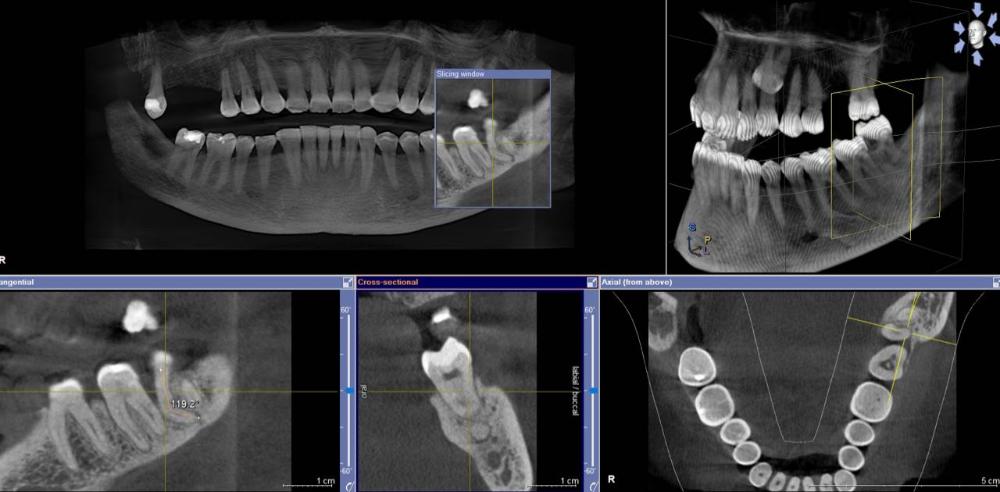

3D x-rays are critically important for diagnostics in dentistry, especially in regards to oral surgery, endodontics (root canal therapy), TMJ/D pathology diagnostics, and implant dentistry. Dr. Nick uses this tech on a daily basis, and many years ago added this very expensive technology to his practice. The CBCT will often catch problems that normal 2-D digital x-rays will not!